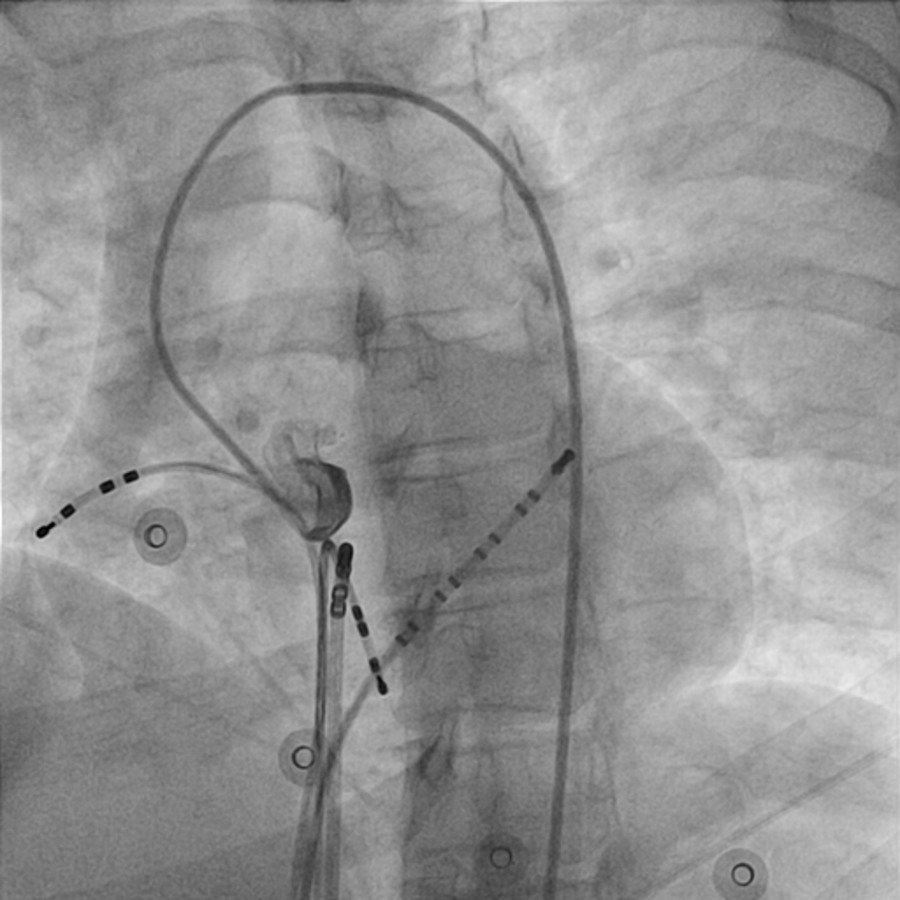

Incremental ventricular pacing

01_vawb.jpg